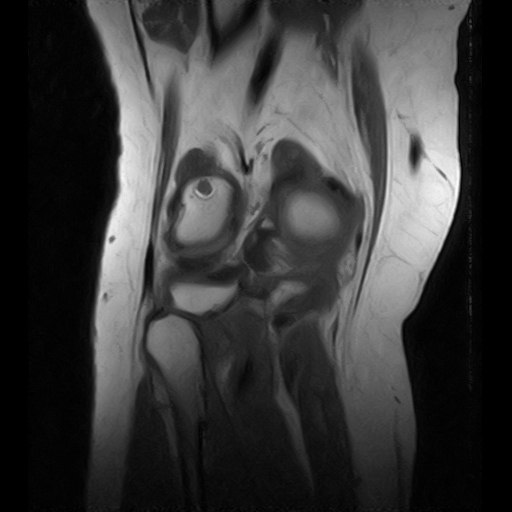

Боли в коленном суставе.Травм не было.Больше информации нет.

Тип: Клиническое наблюдение

Область: Скелетно-мышечная система

Модальность: МРТ

Дата: 20.03.2019 - 21:34